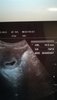

Kochane kobietki, dzisiaj rano byłam na kontroli. Fasolka ma 10.6mm i pięknie bijące serduszko <3 Kolejna wizyta za 3 tyg. Teraz zamiast Duphastonu - Luteina dopochwowo. Mam jeszcze więcej leżeć. Ginekolog zrobił mi od razu USG nerek z uwagi na kamicę prawej nerki i pieczenie w cewce. Mam brać urosept i fitolizynę. W razie większych boleści brzucha nospa 3x1 tab. Dostałam skierowanie na badania prenatalne, badanie moczu, morfologię krwi + m.in. toksoplazmoza, HIV, kiła, TSH. Poprosił też, abym udała się znów do endokrynologa mimo tego, że byłam na kontroli w czerwcu br. Mam łagodny nowotwór na lewym płacie 1 x1,2cm, trzeba kontrolować czy nie rośnie pod wpływem zmian hormonalnych w ciąży.

Załączniki

• IMG_20190821_090959.jpg

Tak, skończone 6tyg równo dziś od OM, początek 7mego tygodnia.

Konkretniej żeby nie zakręcić: 6tyg 1dzien. I serce widziałam, nie słyszałam jeszcze - pulsowanie było widoczne :)